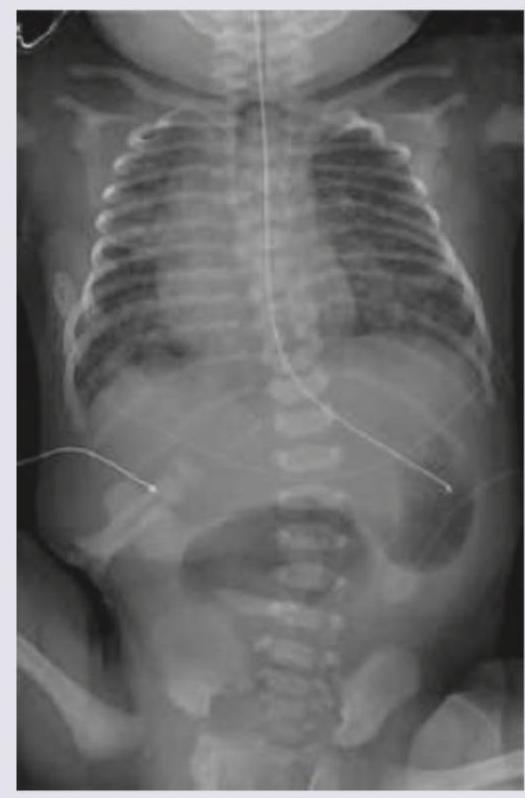

A baby on day 4 of its birth presents with repeated vomiting. The vomiting is bilious in nature. What is the most possible diagnosis as per the infantogram?

Explanation: ***Duodenal atresia*** - The infantogram shows the classic "double bubble" sign, indicating a distended stomach and a dilated duodenum separated by the pylorus. This is pathognomonic for **duodenal atresia**. - **Bilious vomiting** in a neonate, especially from day 1-2 of life, is a key clinical feature of duodenal atresia due to the obstruction being distal to the ampulla of Vater. *Hypertrophic obstructive pyloric stenosis* - This condition typically presents around **3-6 weeks of age** and is characterized by **non-bilious projectile vomiting**. - Radiologically, it would show a distended stomach but not a dilated duodenum; an ultrasound showing a thickened and elongated pyloric channel is diagnostic. *Jejunal atresia* - Jejunal atresia presents with **multiple dilated loops of small bowel proximally** due to the obstruction and air-fluid levels, often leading to a "triple bubble" or multiple air-fluid levels but not the distinct double bubble sign. - While it causes bilious vomiting, the imaging pattern is different from what is seen in the provided infantogram. *Meconium ileus* - This condition is typically associated with **cystic fibrosis** and presents with abdominal distension, failure to pass meconium, and bilious vomiting. - The infantogram would show multiple dilated loops of bowel of varying caliber, often with a "ground glass" appearance due to tenacious meconium, and typically no air-fluid levels or a distinct double bubble.